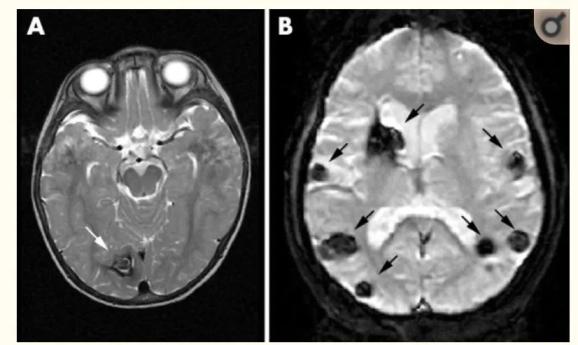

(3)影像学检查:首选的检查方法为MRI,建议包括GRE及SWI序列,以显示微小病灶和可能存在的发育性畸形。

图7 A:T2加权MRI提示右枕叶单发海绵状血管畸形;B:梯度回波T2加权成像提示多发海绵状血管畸形(4)治疗:无症状患者一般建议采取保守治疗,多发的无症状患者也不建议进行外科处理。对于症状性、有出血史且位于浅部手术易于切除的患者,建议积极手术处理,尤其是位于非功能区的患者。症状性深部病灶建议结合并且具体考虑。